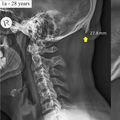

Are Teens Growing Horns Because of Their Smartphones?! Em, Nope.

Recent articles online have claimed that teens using their smartphones constantly are developing so called 'horns' on their skulls. But all may not be what it seems. Dr. Mariana Kersh is an Assistant Professor in the Department of Mechanical Science and Engineering at The University of Illinois at Urbana-Champaign and popped into Room 104 to talk some sense.